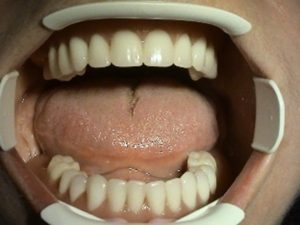

– positive aesthetic effect on facial expression,

charming

and new smile provides better quality of life and restoration of

self-confidence not only

in private life, but also on social and professional level

3. PHASE – fabrication of temporary solution